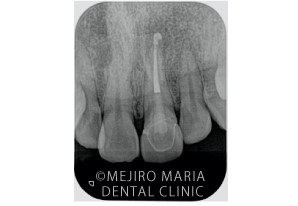

_初診時のX線写真.jpg)

他院にてセラミック(被せもの)を入れるも装着後の違和感が消えず、来院されました。治療の経緯を聞くと、根管治療(歯の根の治療)を行ったが翌日から治療箇所の痛みが増幅し、根尖部付近が大きく腫れ上がったそうです。(写真の赤丸部分)。

_RCF(根幹補充)後のX線写真-1.jpg)

まず精密根管治療から開始しました。精密根管治療の終了後には、歯肉の腫脹や痛みは改善されました。仮歯を入れて3ヶ月間経過観察を行い、その間に、今回のもう一つのご希望である、セラミックの見た目を改善する治療を進めました。